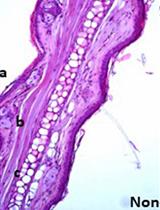

Figure 1. Representative cysts staining from uninfected and infected CBA mice brain with Toxoplasma gondii parasites. Two months after i.p. infection of CBA mice with 1,000 ΔKu80-ΔHXGPRT (PRU) tachyzoïtes, brains were collected, homogenized in 4 ml of PBS and ¼ of each brain suspension was used for the labeling of cyst walls with the D. biflorus-FITC lectin and analyzed by high content screening microscopy (Scan^R Olympus). A) Photo (4x objective) of a CBA infected mouse brain. Three stained cysts are present in this field. B) Uninfected CBA mouse brain (4x objective) no cysts are visible but only brain debris. C) Representative panel of stained cysts obtained from infected CBA mouse and detected by (4x objective) microscopy. Cysts are zoomed to detect potential false positive as in A6.